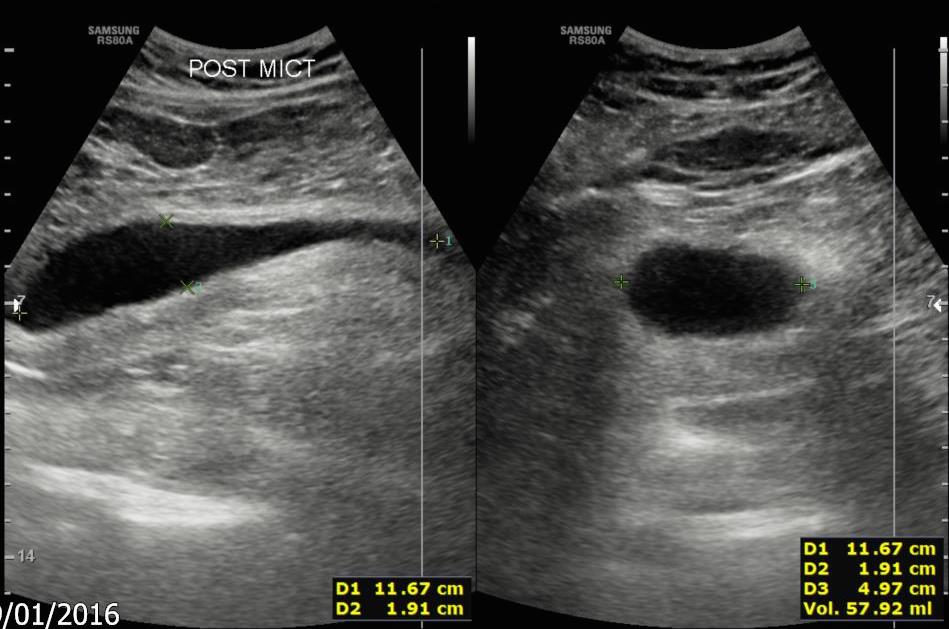

Fig 4. Post micturition views of the bladder in (a) longitudinal and (b) transverse views. |